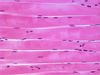

What type of tissue type and sub-type is this? What are its characteristics? Where is it located?

Type: Muscle, cardiac

Description: Cells are branched, lightly striated, and uninucleated, joined by intercalcated discs that may not be visible

Location: Walls of heart (blood circulation)